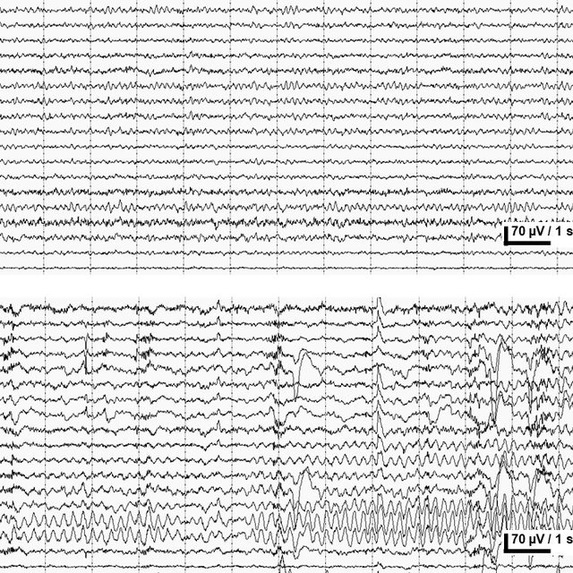

We learned the usage of TensorFlow, React.JS framework, Flask, and server-client communication knowledge. We also did a direct comparison of the credible EEG statistics from research literature by employing MATLAB plot and analysis functions, which provided a even more straightforward visualization of the difference in EEG trends among epilepsy patients and normal people.

We use credible EEG dataset from Brown University Epilepsy Database collected from epilepsy seizure patients. We use two sets of data: one set of non-epileptic, eyes-open, one set of epileptic, in-seizure. Each set of EEG dataset consists of 200 recordings, in which each consists one channel of electric voltage data for 4097 datapoints.